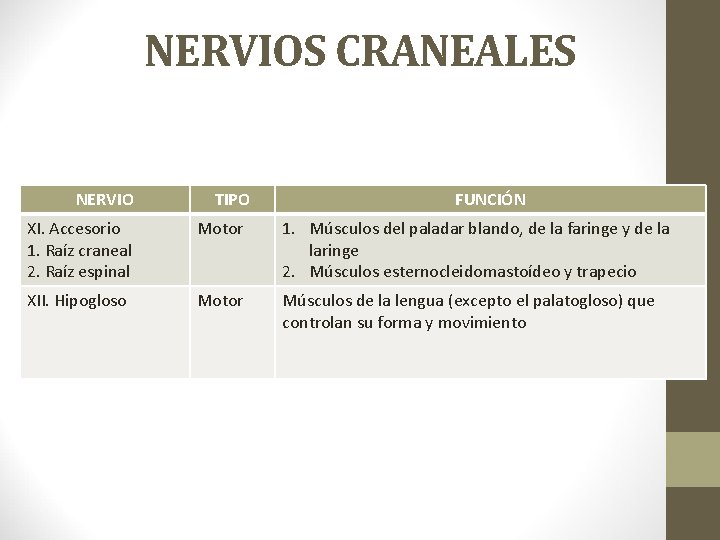

NERVIOS CRANEALES NERVIO TIPO FUNCIÓN XI. Accesorio 1. Raíz craneal 2. Raíz espinal Motor 1. Músculos del paladar blando, de la faringe y de la laringe 2. Músculos esternocleidomastoídeo y trapecio XII. Hipogloso Motor Músculos de la lengua (excepto el palatogloso) que controlan su forma y movimiento